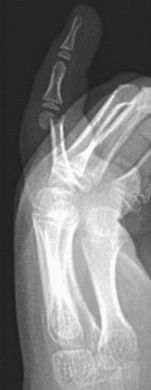

C. Fractura de Seymour

Es un tipo especial de fractura de la falange distal que se caracteriza por ser una lesión del lecho ungueal con una fractura expuesta (Figura 20). El tratamiento debe ser agresivo, como el de una fractura abierta, irrigación y desbridamiento, reducción y estabilización de la fractura fisaria, reparación del lecho ungueal, reubicación de la matriz en su surco. La inmovilización será en extensión durante 4-5 semanas, sin olvidar el tratamiento antibiótico.

Figura 20: a-d, Fractura de Seymour: epifisiolisis falange distal con lesión del lecho ungueal asociada. (Imágenes cedidas por Dra. Pérez López)